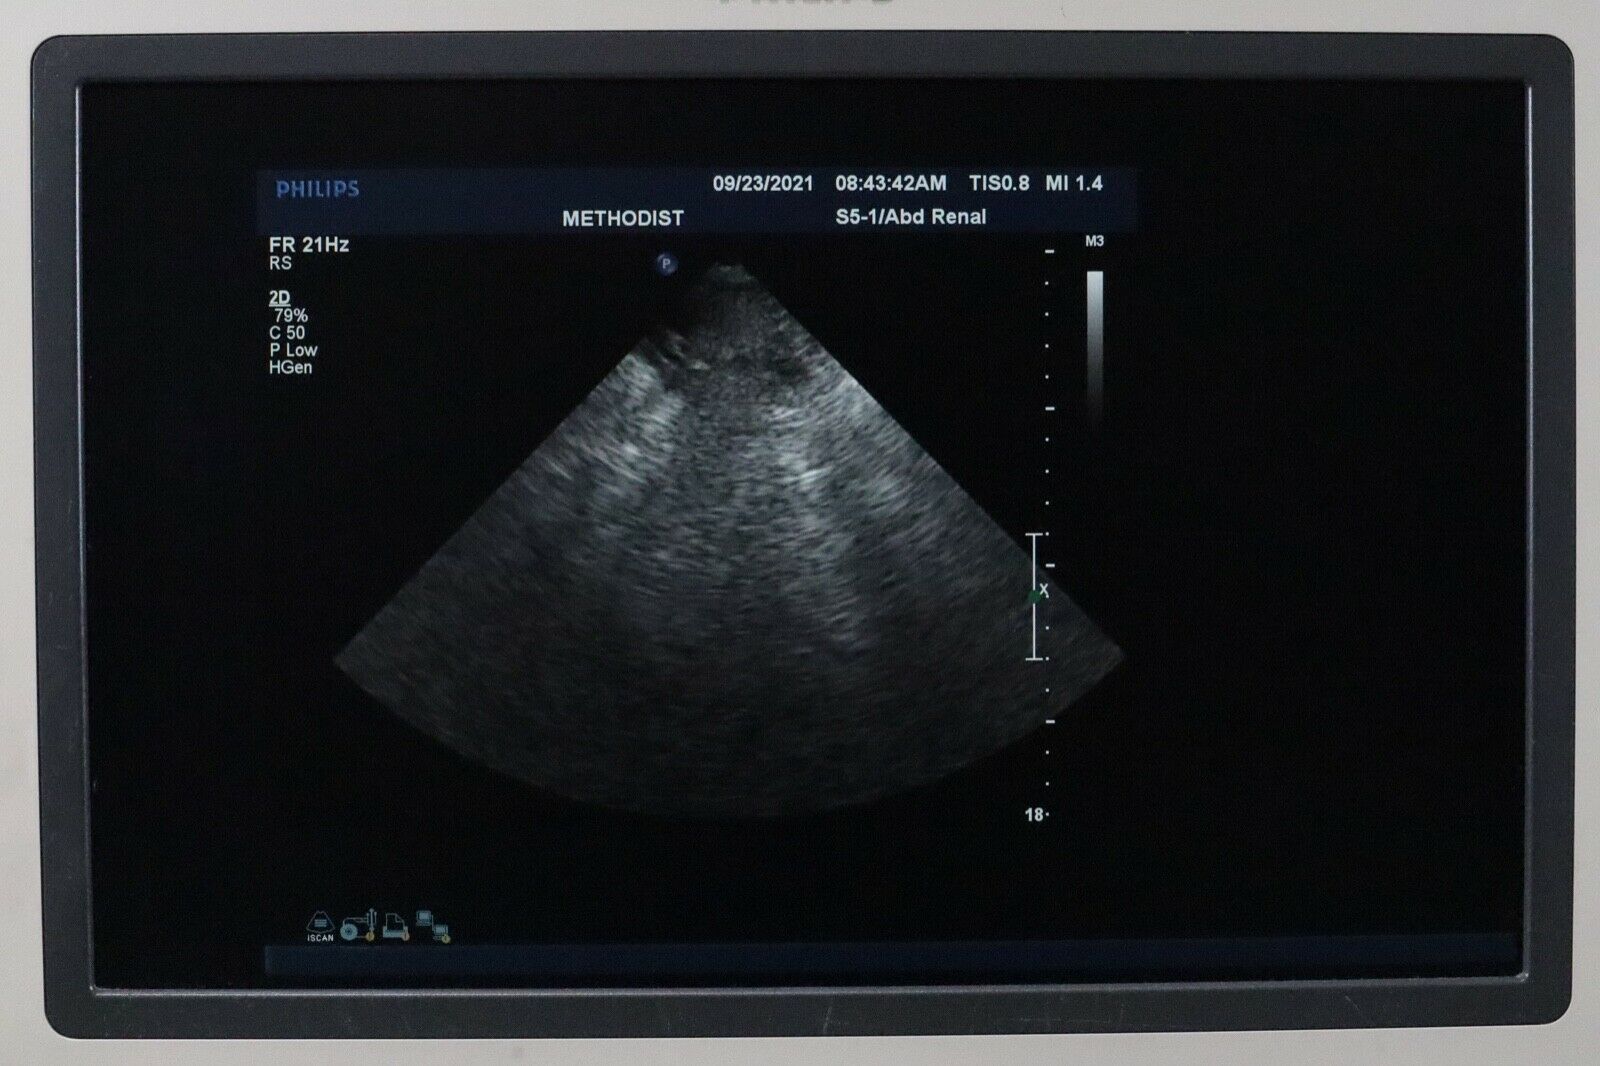

PHILIPS S5-1 SECTOR ARRAY ULTRASOUND PROBE

The Philips S5-1 Sector Array Ultrasound Probe is a high-performance imaging transducer designed for a range of clinical applications, including abdominal, cardiac, and obstetric/gynecological imaging. With a frequency range of 1-5 MHz, this probe offers excellent tissue penetration for deeper imaging, while maintaining high-resolution images for accurate diagnostics. The sector array design enables the probe to capture detailed images from a small footprint, making it ideal for patients with challenging body types or when accessing confined anatomical areas.

The Philips S5-1 probe is widely used for echocardiograms and other cardiovascular applications, as well as abdominal and obstetric exams. Known for its durability and reliability, it is compatible with Philips ultrasound systems and supports a variety of imaging modalities such as Doppler and 2D imaging. The S5-1 is designed for ease of use, providing clinicians with clear, real-time images to guide accurate diagnoses and treatment decisions.